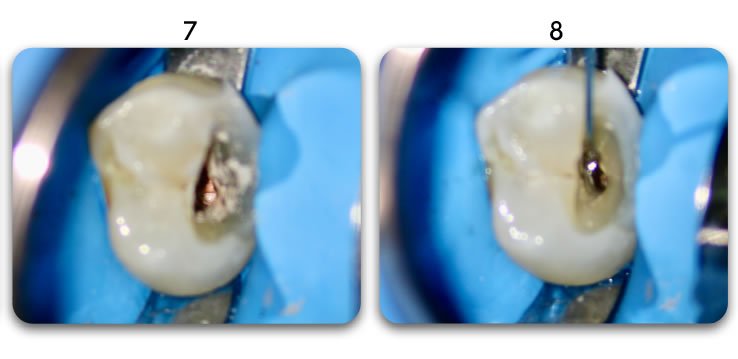

Post removal process:

Use a small round of flame shaped diamond bur to drill in the center of the canal to allow for insertion of a coarse grit ultrasonic tip that will remove remaining cement and post strands.